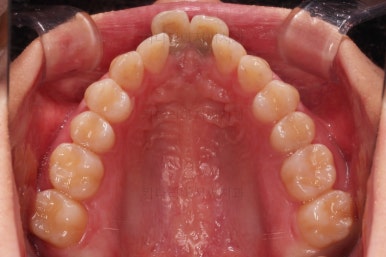

1. 초진

부산개방교합 키다리아저씨치과에 처음 내원 시 입안의 모습입니다.

전반적으로 치열이 삐뚤고요.

앞니쪽이 다물어지지 않는 개방교합(오픈바이트, open bite) 을 보였습니다.